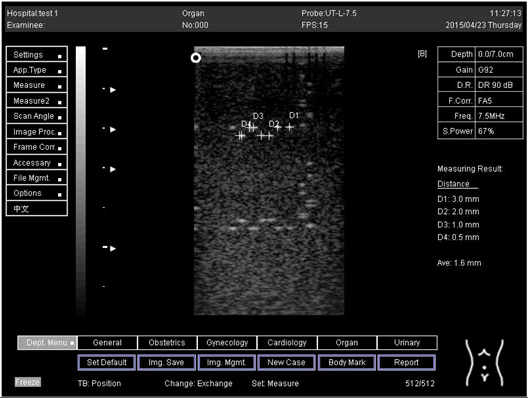

5.0Axial resolution

Biomimetics 07 00130 i011

D1 = 3.0

D2 = 2.0

D3 = 1.0

D4 = 0.5

5.0 Lateral resolution

Biomimetics 07 00130 i012